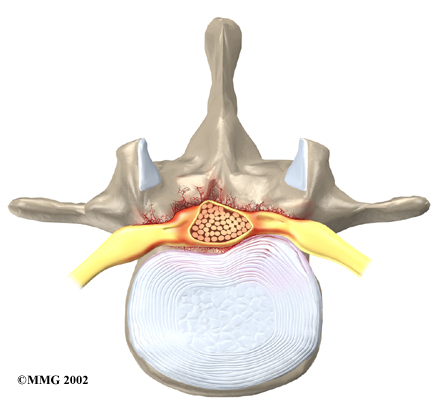

Disc herniation: Spinal stenosis can occur when an intervertebral disc in the low back herniates (ruptures). Normally, the shock-absorbing disc is able to handle the downward pressure of gravity and the strain from daily activities. However, if the pressure on the disc is too strong, such as landing from a fall in a sitting position, the nucleus inside the disc may rupture through the outer annulus and squeeze out of the disc. This is called a disc herniation. If an intervertebral disc herniates straight backward, it can press against the nerves in the spinal canal, causing symptoms of spinal stenosis.

Disc Herniation